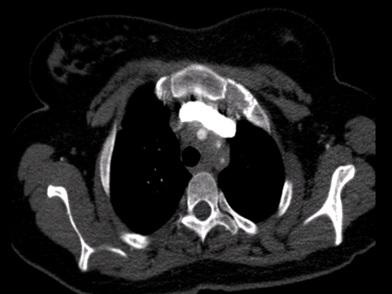

CT-angiografie met een transversale doorsnede van de aortaboog van patiënte

Een 23-jarige vrouw komt op de polikliniek Interne Geneeskunde. Wegens een toename in de frequentie van haar migraine-aanvallen had de huisarts een bètablokker voorgeschreven. Vervolgens krijgt patiënte klachten van duizeligheid en zwarte vlekken voor haar ogen bij opstaan uit zittende of liggende houding, na fysieke inspanning en bij overgang van koud naar warm. Op de CT-angiografie wordt een opmerkelijke afwijking gezien.